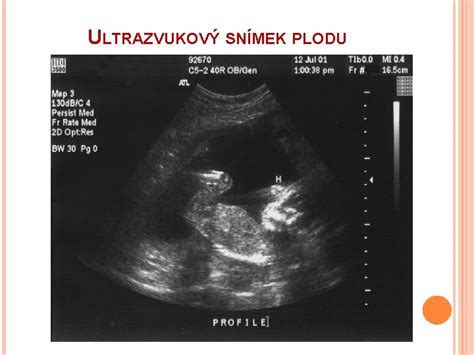

- Počas tehotenstva: Ultrazvuk je neoddeliteľnou súčasťou sledovania tehotenstva. Poskytuje cenné informácie o zdraví a vývoji plodu, umožňuje určiť gestačný vek, identifikovať viacpočetné tehotenstvo, skontrolovať polohu placenty a včas odhaliť prípadné vrodené vady.

Ultrazvukové Vyšetrenie Tehotných Žien

Ultrazvukový skríning tehotných žien je bezpečná a spoľahlivá metóda na hodnotenie stavu plodu a včasné odhalenie možných patológií jeho vývoja.

Plánované ultrazvukové skríningy počas tehotenstva:

- Prvý skríning (10. - 13. týždeň): Pomáha určiť približný dátum pôrodu, vylúčiť mimomaternicové tehotenstvo, posúdiť anatomický vývoj plodu, identifikovať ťažké vrodené patológie chrbtice a skontrolovať tvar a tonus maternice.

- Druhý skríning (18. - 21. týždeň): Podrobne sa skúmajú kosti plodu, miecha, mozog, vnútorné orgány a tvár. V tomto štádiu je možné diagnostikovať rázštep podnebia, rázštep chrbtice, srdcové abnormality a iné závažné defekty. Lekár môže tiež určiť pohlavie dieťaťa, množstvo plodovej vody a posúdiť stav placenty.

- Tretí skríning (30. - 34. týždeň): Zameriava sa na potvrdenie normálneho vývoja plodu, jeho krvného obehu, dýchacej a motorickej aktivity. Hodnotí sa stav placenty, ktorý priamo súvisí so zdravím plodu.